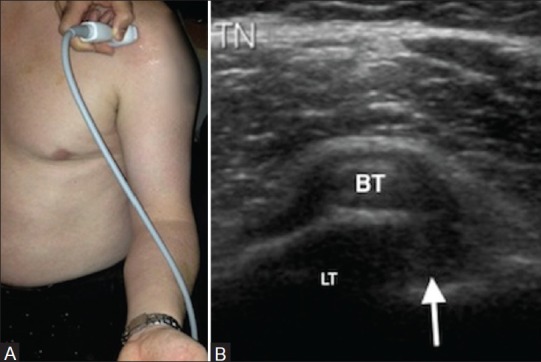

Por otro lado, la exploración en eje corto se realizará con el siguiente posicionamiento de la sonda:

En este eje, el corte de referencia que debes buscar en el ecógrafo es este:

Así es como se verían las alteraciones del bíceps en ecografía:

Ecografía axial del tendón de la porción larga del bíceps, donde se aprecia líquido y engrosamiento sinovial alrededor de su vaina (flecha).

Subluxación medial del tendón de la porción larga del bíceps, visible con la corredera bicipital vacía (flecha), hallazgo sugestivo de inestabilidad del bíceps. LT: troquín.